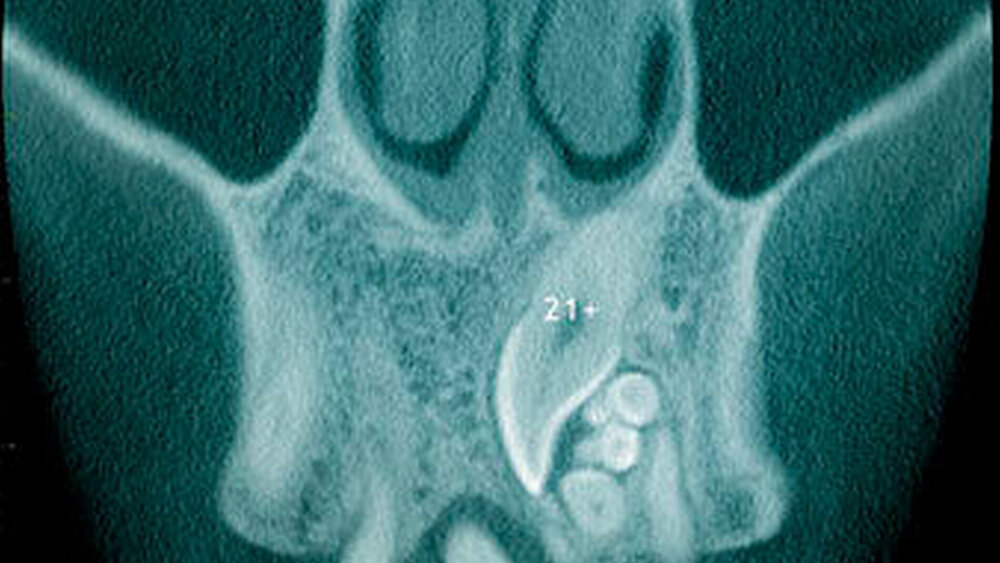

Überzählige Zähne werden nach ihrer Lage im Zahnbogen und auch aufgrund ihrer Morphologie eingeteilt. Basierend auf der Lage unterscheidet man bei überzähligen Zähnen zwischen Mesiodens (Oberkiefer median), zwischen den zentralen Inzisiven (Abbildungen 5 und 6), einem zusätzlichen Schneidezahn (zentral oder lateral), Eckzahn, Prämolar (Abbildung 7), Paramolar und Distomolar (Abbildungen 8). Mesiodentes werden am häufigsten dia- gnostiziert, wobei Prozentsätze zwischen 38,8 Prozent bis 86,3 Prozent der überzähligen Zähne in der Literatur zu finden sind [Salcido-García et al., 2004/38,8 Prozent, Fernández Montenegro et al., 2006 /46.9 Prozent; Mossaz et al., 2014/48.5 Prozent; Ferrés-Padró et al., 2009/53.2 Prozent; Schmuckli et al., 2010/75 Prozent; Rajab Hamdan 2002/83.2 Prozent; Liu et al., 2007/86.3 Prozent]. Überzählige Prämolaren und seitliche Schneidezähne sind die zweithäufigste Gruppe der überzähligen Zähne. Überzählige Eckzähne, Paramolaren und Distomolaren dagegen gelten als eher selten [Rajab Hamdan, 2002; Salcido- García et al., 2004; Liu et al., 2007; Ferrés-Padró et al., 2009; Schmuckli et al., 2010; Mossaz et al., 2014]. Einzig eine Spanische Gruppe [Fernández Montenegro et. al., 2006] berichtete, dass Paramolaren und Distomolaren insgesamt relativ häufig seien (18 Prozent, beziehungsweise 5,6 Prozent). Überzählige Zähne kommen im Ober- und Unterkiefer vor, wobei sich überzählige Schneidezähne in der Regel im Oberkiefer, überzählige Prämolaren sich dagegen eher im Unterkiefer befinden [Fernández Montenegro et al., 2006; Ferrés-Padró et al., 2009; Mossaz et al., 2014]. Überzählige Molaren wiederum treten normalerweise im Oberkiefer auf [Cassetta et al., 2014; Kaya et al., 2014].

Bei überzähligen Zähnen werden vier morphologische Typen unterschieden: konisch (Abbildung 9), tuberkulär (höckerförmig; Abbildung 10), überzählige Zähne mit identischer Zahnform (Abbildung 11) und Odontom (Abbildung 12) [GARVEY et al. 1999]. Der konische überzählige Zahn ist ein kleiner, zapfenförmiger Zahn und zudem der häufigste Fall im bleibenden Gebiss [Rajab Hamdan 2002, Liu et al. 2007, Gündüz et al., 2008; Ferrés-Padró et al., 2009; Hyun et al., 2009; Schmuckli et al., 2010; Mossaz et al., 2014]. Er kommt oft zwischen den oberen zentralen Schneidezähnen vor und entwickelt sich gleichzeitig zur Wurzelbildung der bleibenden Schneidezähne. Konische überzählige Zähne führen meist nicht zu einer Durchbruchstörung oder -behinderung der zentralen Schneidezähne. Tuberkuläre, überzählige Zähne sind größer als der konische Typ und besitzen einen zusätzlichen charakteristischen Höcker oder Tuberkel der Zahnkrone. Sie kommen oft gepaart vor und liegen in der Regel palatinal der oberen mittleren Schneidezähne. Im Gegensatz zu konischen überzähligen Zähnen brechen die meisten tuberkulären nicht in die Mundhöhle durch und es kommt nicht selten zur Durchbruchstörung oder -behinderung der zentralen Schneidezähne [Mason et al., 2000; Minguez-Martinez et al., 2012]. Überzählige Zähne mit identischer Zahnform sind Zähne, welche vom eigentlichen Zahn in der Lage (also in der Zahnreihe gelegen) und Form nicht zu unterscheiden sind.

Der letzte Typ der überzähligen Zähne ist das Odontom. Obwohl das Odontom gemäß WHO-Klassifikation als odontogener Tumor eingeteilt wird [Praetorius Piatelli, 2005], sind sich heute die meisten Autoren darin einig, dass ein Odontom keine benige Neoplasie darstellt, sondern eine hamartomatöse Fehlbildung ist [Garvey et al., 1999; Wang Fan, 2011]. Beim Odontom können zudem klinisch-radiologisch sowie histologisch zwei Arten unterschieden werden: Das komplexe Odontom, bei welchem Zahnhartgewebe als diffuse Masse, das heißt gänzlich unorganisiert angelegt ist, und das zusammengesetzte Odontom, welches aus multiplen zahn- ähnlichen Strukturen besteht, die jeweils bindegewebig abgegrenzt sind.